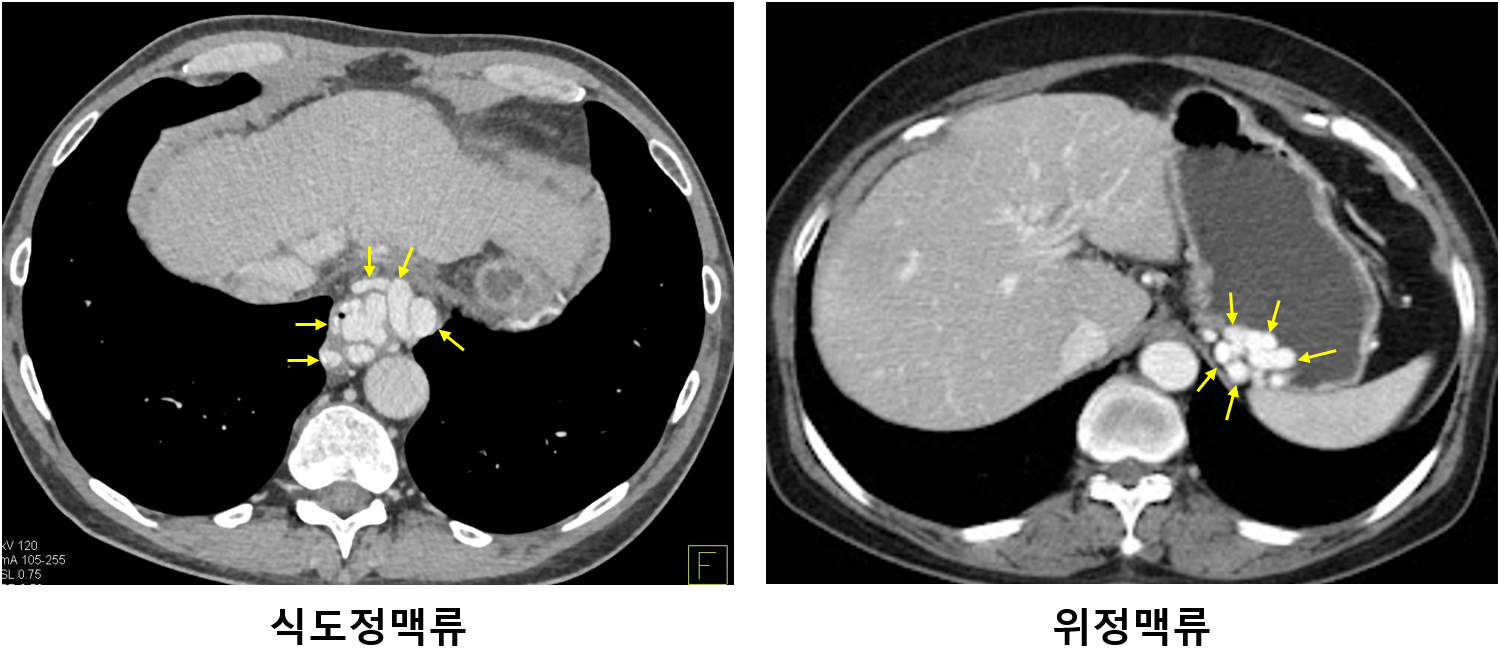

4) 진단

(1) 상부위장관 내시경(EGD): 1st line

① 정맥류의 존재 및 위치를 확인

② 활동성 출혈 여부를 확인

(2) CT: 위정맥류가 확인될 경우 혈관 anatomy를 확인하기 위해 시행 가능